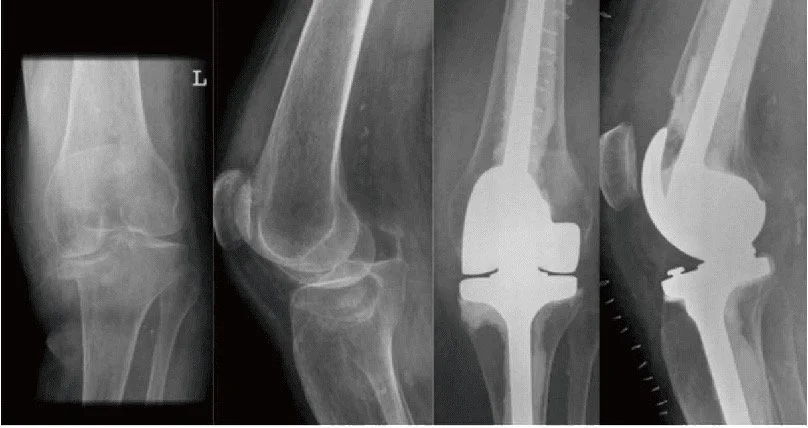

During TKR surgery for tibial plateau fractures, the orthopedic surgeon makes an incision to access the knee joint. The damaged bone and cartilage are removed from the tibial plateau and femoral condyles. Metal or plastic components are then secured to the bone using cement or press-fit techniques. These components serve as prosthetic replacements for the natural joint surfaces, allowing for smooth movement and weight-bearing.

total knee replacement following tibial plateau fracture